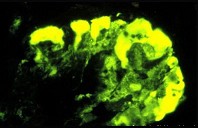

- 单项选择题图-1为HE染色,图-2为PAS染色, 图-3免疫荧光镜下可见IgM团块状沉积于病灶区,图-4电镜下可见上皮细胞足突广泛融合, 系膜增生(M)。阅读这些病理图片,诊断其病理类型是 ( )

A、系膜增生性肾小球肾炎

B、膜增生性肾小球肾炎

C、局灶性节段性肾小球硬化

D、肾小球轻微病变

E、局灶性肾炎